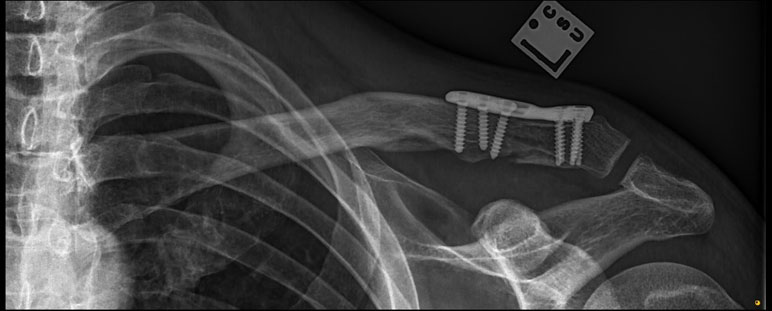

What do clavicle fractures look like on X-ray?

Below are examples of typical fractures that benefit from surgery.

Click an image to enlarge